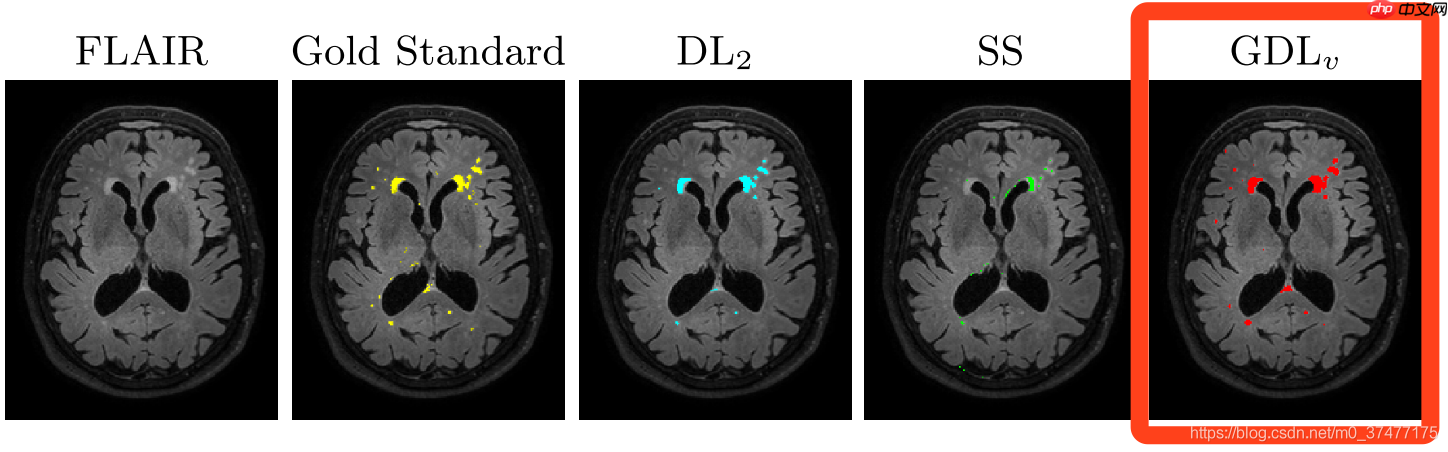

效果

缺点: 在AnatomyNet中提到GDL面对极度不均衡的情况下,训练的稳定性仍然不能保证